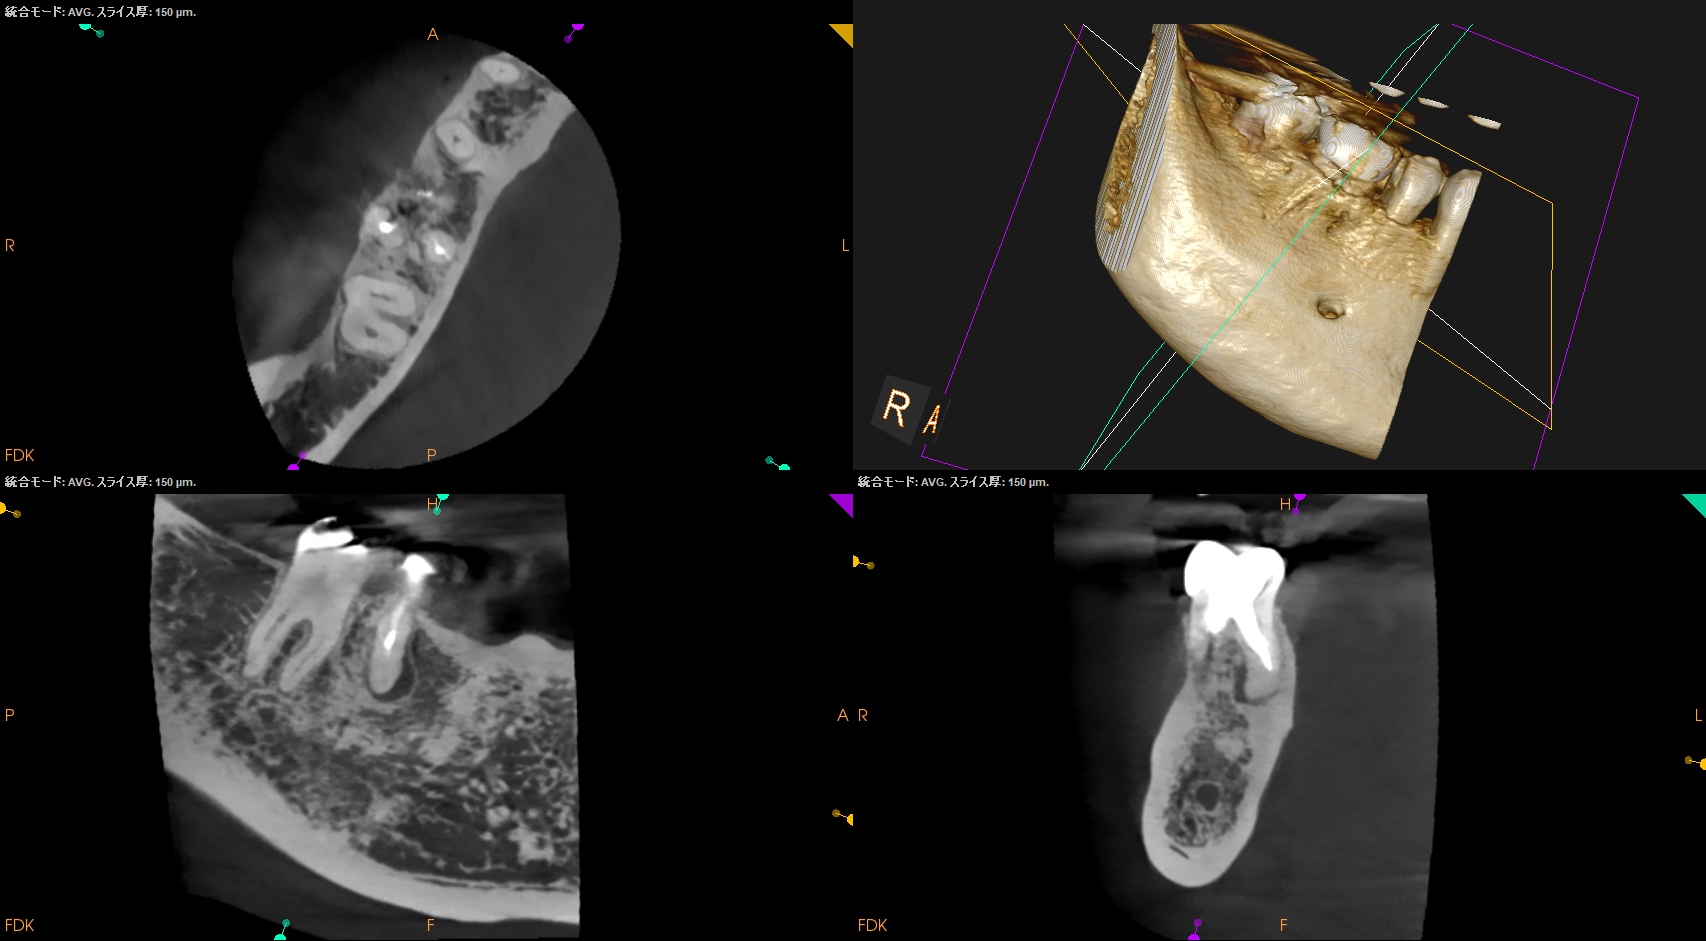

#30 M Apicoectomy, D+Radix Re-RCT 2yr recall(2025.10.17)

Radix

初診時、1年後と比較した。

トランスポーテーションしたMは劇的に治癒している。

Dも然りだ。

が、トランスポーテーションしているRadixはまだ治癒途中だろう。

が、患者さんに症状もないことからこの歯の状況はさらに2年後に経過を見せてもらうこととなった。